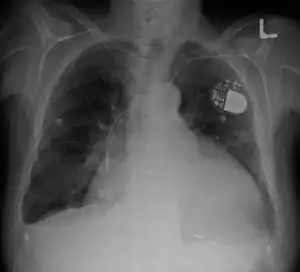

| Cardiomegaly on chest X-ray with a pacemaker | |

- Pacemaker: Coordinates the contractions between the left and right ventricle. In people who may be at risk of serious arrhythmias, drug therapy or an implantable cardioverter-defibrillator (ICD) may be used.